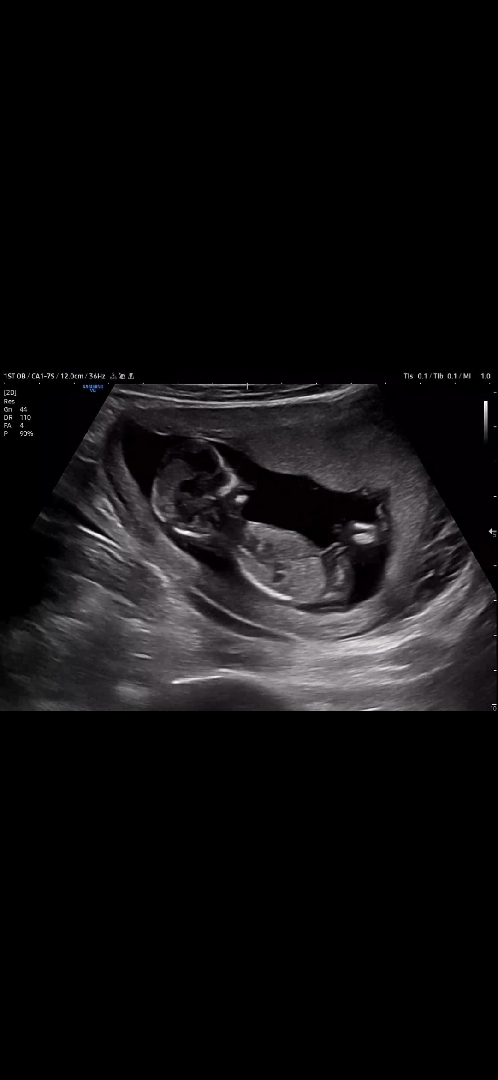

12주 5일인데 각도법 투표 부탁드려요🥰

이제 15주라 곧 알게 되겠지만 그동안 궁금하네요 한번 봐주시면 감사하겠습니다!!